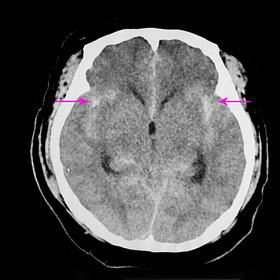

Liberal vs restrictive RBC transfusion in brain-injured patients: meta-analysis

Studies of red cell transfusion thresholds for “acute brain injury” tend to lump together patients with strokes, traumatic brain injuries, and sometimes anoxic-hypoxic encephalopathy. In this heterogeneous group, liberal transfusion to higher hemoglobin targets (e.g., 9 to 10 g/dL) appears to lead to better outcomes than restricting transfusion.

A new meta-analysis of six randomized trials (n=2,497) concluded that a liberal transfusion strategy led to higher rates of favorable neurologic outcomes (RR 0.89), and trends toward improved mortality and length of stay.

When TBI patients (n~1,400) were analyzed as a separate subgroup, similar results were found to the overall population. Significant heterogeneity remained, though, with caution advised in interpreting the results.